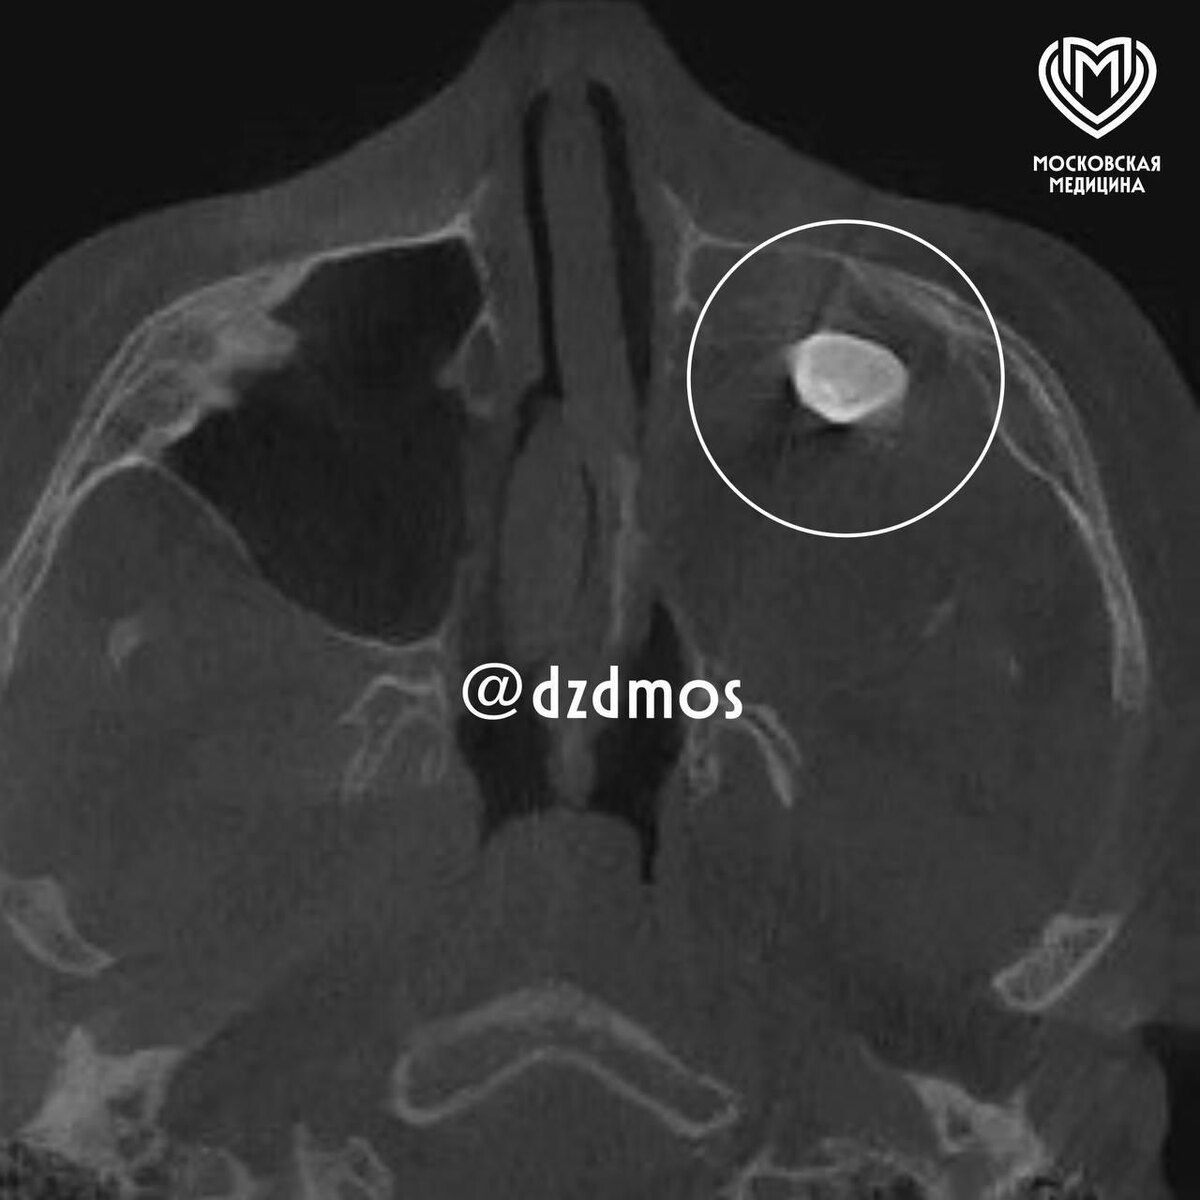

Московские врачи удалили подростку выросший в носу зуб, сообщает столичный департамента здравоохранения

Во время операции врачи обнаружили новообразование, внутри которого и находился зуб. Позже выяснилось, что это доброкачественная тератома.